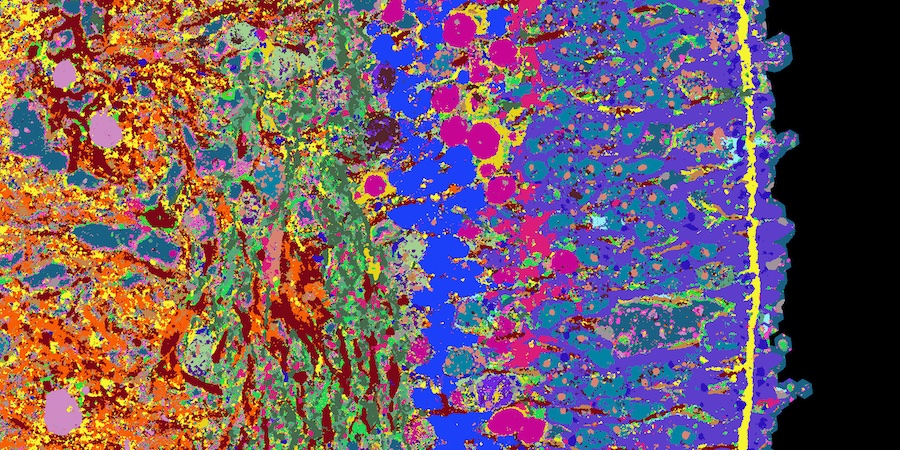

Detail of a cross-section of a retinal organoid. Different tissue structures are made visible with different colours. Credit: ETH Zurich/Nature Biotechnology.